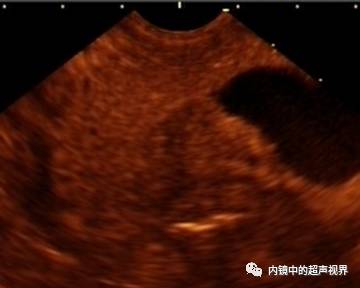

再说伪彩,它把黑白图像处理成黑橙、黑绿、黑蓝、黑粉等图像,一定程度上改变了图像的视感,类似于FICE、iSCAN等后处理光学染色功能,萝卜白菜各有所爱,喜欢哪个直接拿走。